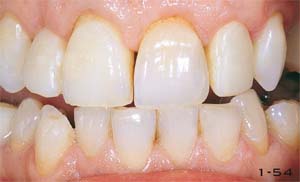

Abb. 1-54 Zustand nach Bleichen und nach Präparation der Zähne für Vollkeramikkronen an den seitlichen und Veneers an den zentralen Schneidezähnen. Das zweite Provisorium, das nach einem Duplikatmodell des Waxups angefertigt wurde, befindet sich in situ.